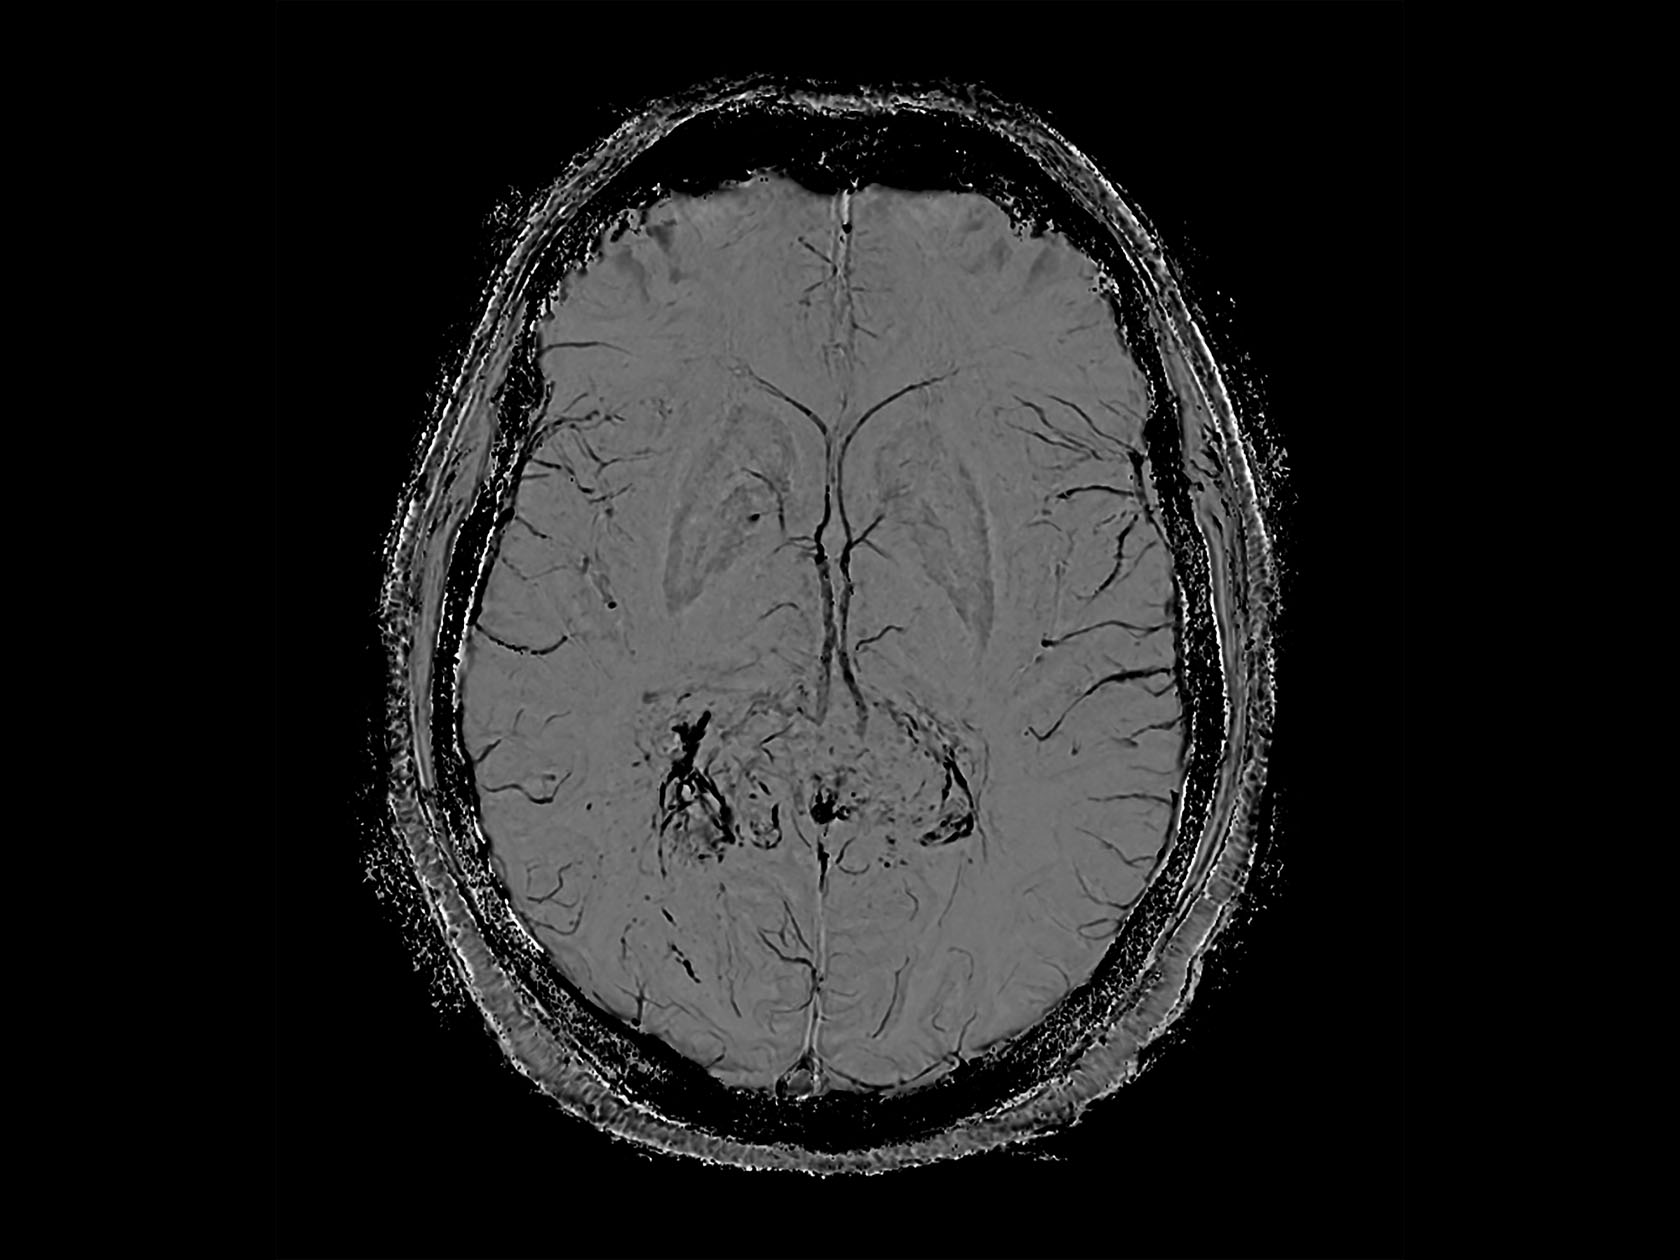

Axial SWIp

-

Axial SWIp (phase)